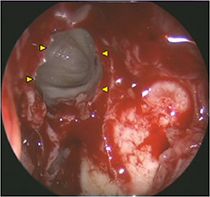

Aspergillom der linken Kieferhöhle (Endoskopisches Bild, 0°-Optik)